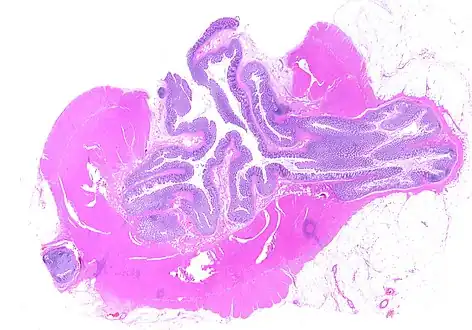

CT scan showing extensive diverticulosis of the sigmoid colon -

Diverticular disease -

Whole slide of a transverse section of the left colon with diverticulosis